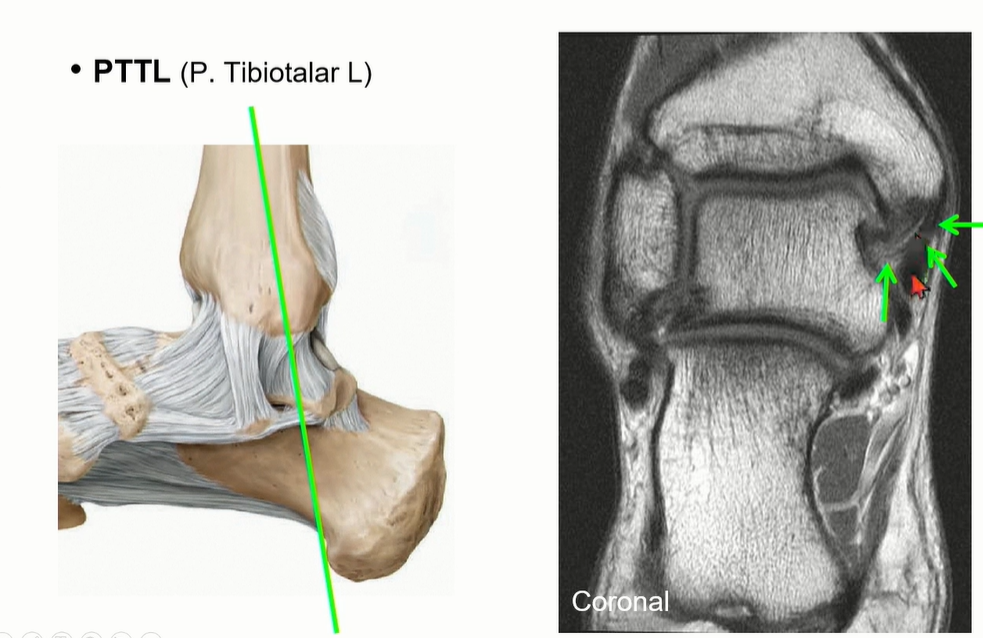

Deep deltoid liagment의 하나인 PTTL의 주행.

ATTL에 비해서 넓어서 영상에서 확인이 용이하다. ligament 사이에 fat이 관찰되는 것이 정상.

coronal cut에서도 fat때문에 straiation이 보이는 것이 정상이다.

녹색으로 표시한 것은 flexor retinaculum으로 deltoid ligament와 오인하지 않도록 조심해야 한다.